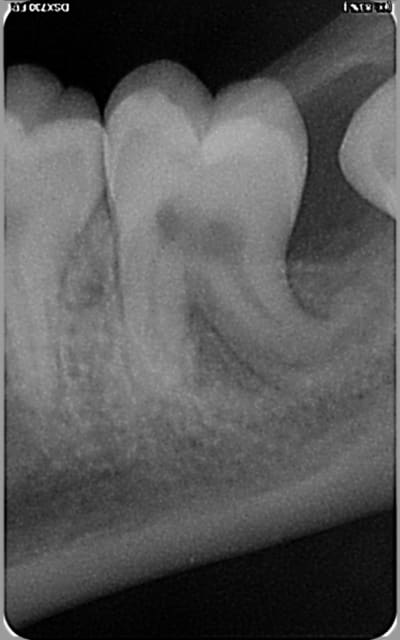

Et voici ce que je trouve sur la 37: une image sombre énorme autour d'une racine plus que courbée.

Après une rétro alvéolaire de complément, la zone sombre semble épargner la racine distale de 37 pour se situer plus sur la 38?!?

Le patient ne présente aucun symptome et la 37 réagit positivement au test au froid.

Un cone-beam me semble indispensable. Un kyste folliculaire depuis la 38 est possible (la lésion semble partir du collet) mais on peut également penser dans cette zone au kyste de furcation vestibulaire.

La lésion ne semble pas liée à 38.

sur la rétroalvéolaire la lesion semble circonscrite à la couronne dent 38 .... kyste folliculaire.... Il me semble que sur la panoramique une deformation plus semble présente... courbure de la racine dent 37...

pas la courbure des racines mais positionnement de la lésion radio clair moins relié à la racine 37 sur la PA